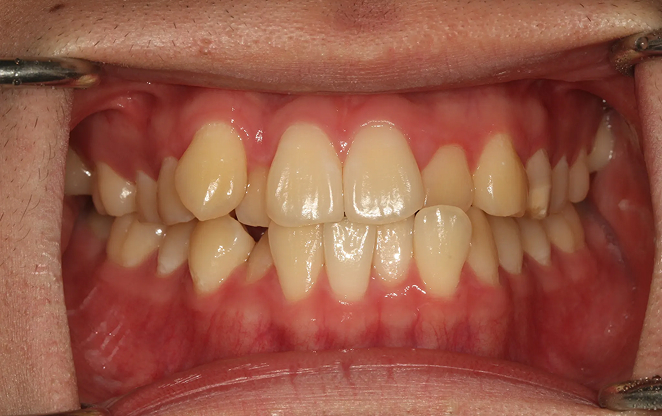

Before

After

비보철 교정은 치아를 뽑거나 보철물을 사용하지 않고,

내 치아 그대로의 아름다움을 지켜가며 교정하는 방법입니다.

불필요한 보철 없이 치아의 배열을 조정해, 자연스럽고 건강한 치아와

균형 잡힌 미소를 찾아가는 과정입니다. 자연스러움 속에서 완성되는

건강한 미소, 비보철 교정으로 그 여정을 시작하세요.